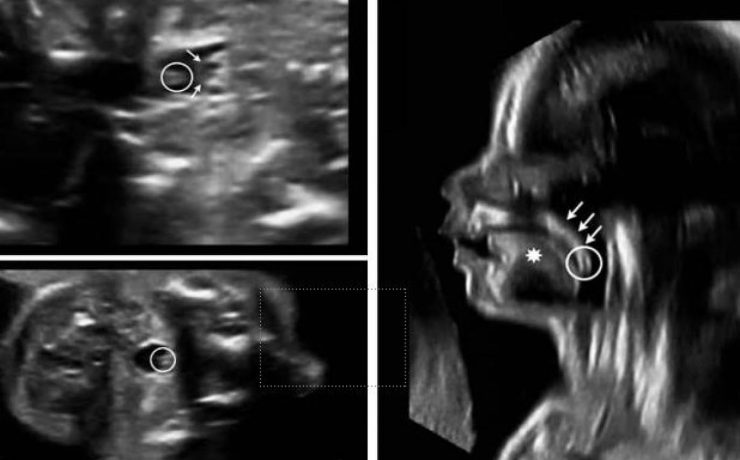

Escrito por Irene Arnanz González en 2014, hace la descripción de una paciente de 94 años quien ingresó a la consulta médica por prurito e ictericia con examen físico sospechoso por lo que se indicó ultrasonido de vías biliares con resultado de vesícula con pared gruesa de hasta 1cm de